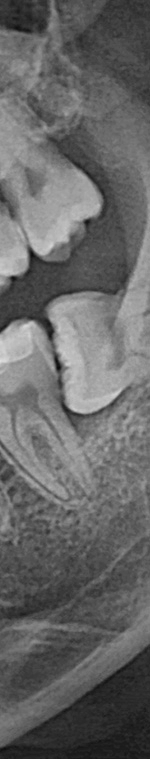

사랑니가 90도로 누워서 난 경우는 수평 매복, 뼈나 잇몸에 사랑니가 완전히 덮여서 아예 보이지 않는 경우는 완전 매복, 일부분만 잇몸이나 뼈에 덮여있는 경우 부분매복이라고 했어요. 대부분의 환자분이 이런 매복 중에 한 가지에 해당하기 때문에 시술이 매우 어려웠어요. 특히 사랑니 주변으로는 구강과 관련된 중요한 신경 조직이 인접하여 있기 때문에 고난이도 시술이라고 할 수 있었어요.

턱 뼈와 치아 사이에 공간이 충분하지 않기 때문에 누워서 올라오거나 매복되어 자라는 경우가 많았어요. 반포치과를 찾는 분들의 사랑니의 경우 매복된 경우도 많고 이가 완전히 잇몸 밖으로 나오지 않아서 일반 치과에서는 발치가 어려웠어요. 사랑니발치가 왜 필요한지 가끔 의문을 가지는 분이 계셨어요. 사랑니발치를 왜 해야 하는지 알려드리겠어요. 사랑니는 다른 치아처럼 바르게 나는 경우도 드물게 있긴 하지만 대부분 어금니 쪽으로 기울어져서 올라오거나, 완전히 수평으로 누워서 자라는 경우도 있었어요. 누워서 자라는 치아는 옆의 치아를 밀어 치열이 비뚤어지고 부정교합을 유발했어요.

만약 사랑니 발치 시술이 잘못되면 사랑니와 인접한 신경 조직에 손상이 오거나 구강 마비와 같은 부작용이 발생할 수 있었어요. 그렇기 때문에 사랑니 발치를 하기 위해 치과를 선택할 때는 신중하게 선택해야 했었어요. 반포치과를 선택하기 전에 발치전문 의료진이 있는지, 경험이 풍부한지 반드시 확인해보시고 결정하셔야 했었어요.

사랑니발치를 하기 위해서는 먼저 파노라마 x선 사진을 통해 발치 시 신경에 영향을 줄 수 있는지 확인하는 과정을 진행했어요. 이 과정을 통해서 충분히 의사와 상담을 한 후 처방전을 발급했어요. 이 때 처방전에는 항생제를 포함하여 발치 후 통증을 대비한 진통제를 처방했어요. 환자에게 충분히 설명한 후에 국소마취를 진행하고 마취가 된 다음에 절개를 최대한 덜 하는 방향으로 수술하여 사랑니를 발치했어요.